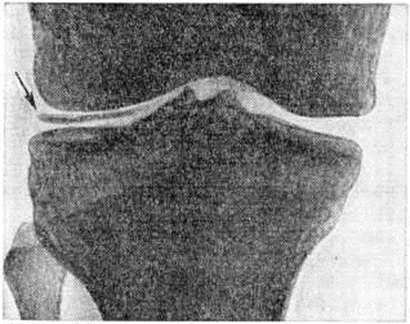

Рентгенологические признаком Псевдоподагра является хондрокальциноз — обызвествление хряща в виде теней или отдельных вкраплений. Обызвествлению при Псевдоподагра подвергается не только гиалиновый хрящ (наиболее часто коленных суставов), но и волокнистая хрящевая ткань (мениски, хрящ лонного сочленения, хрящевой диск в области кистевого сустава, межпозвонковые диски), а в некоторых случаях и соединительная ткань капсулы суставов, сухожилий и сумок. Наиболее типичен для Псевдоподагра хондрокальциноз менисков коленных суставов (рисунок). Рентгенологические исследование имеет важное диагностическое значение при Псевдоподагра В ряде случаев хондрокальциноз поражённого в данный момент сустава при Псевдоподагра может отсутствовать, поэтому для уточнения диагноза необходимо исследование других наиболее частых локализаций хондрокальциноза, указанных выше. При Псевдоподагра часто наблюдаются рентгенологическое изменения, характерные для артроза — деструкция суставного хряща и развитие остеофитов (смотри полный свод знаний).

Рис

Рентгенограмма коленного сустава при псевдоподагре (прямая проекция): линейное затемнение в суставной щели (указано стрелкой), обусловленное обызвествлением наружного мениска и суставного хряща.